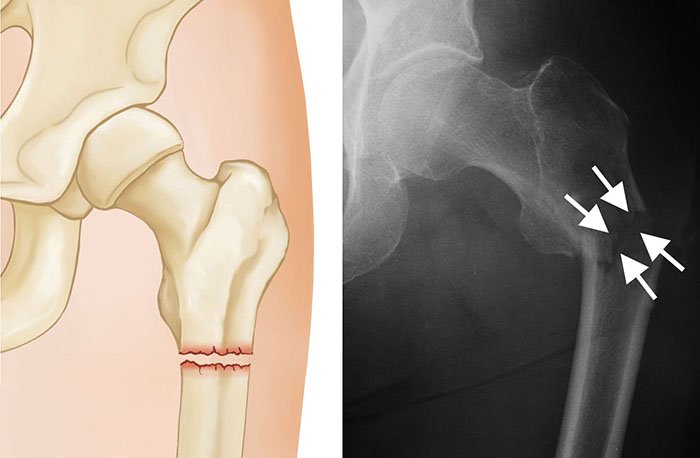

– Υποτροχαντήριο κάταγμα (κάτω από τον μικρό τροχαντήρα)

– Ακτινογραφία λεκάνης και ισχίου

– CT ή MRI (αν η ακτινογραφία δεν δείχνει κάταγμα αλλά τα συμπτώματα επιμένουν)